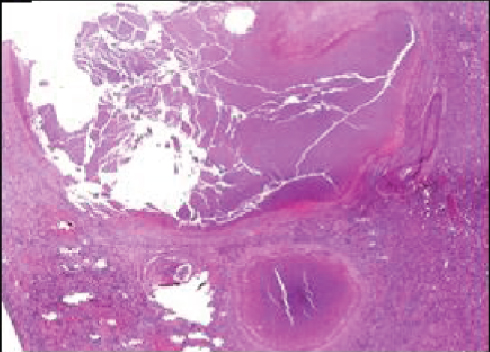

The patient subsequently presented with anti-TB drug toxicities: haemolytic anaemia (related to rifampicin) and blurred vision (due to ethambutol), both in the 2nd month of treatment resulting in a change of therapy. At this time, the patient presented disseminated disease involving grafts, lungs, CNS, and thyroid.The clinical deterioration of the patient imposed immunosuppressive cessation, leading to acute cellular rejection of the grafts, and dual graft loss with return to hemodialysis and insulin therapy. The patient underwent exploratory laparotomy with a surgical finding of caseating necrosis all over the mesenterium and around pancreatic graft, but affecting the renal graft. The removal of the renal graft was the only viable treatment encountered (Figure 2). After several ultrasound guided punctures to drain intra-abdominal TB abscesses and 18 months of anti-TB therapy, the patient was considered cured. However, he died from complications related to ESRD and dialysis, two years after transplantation.